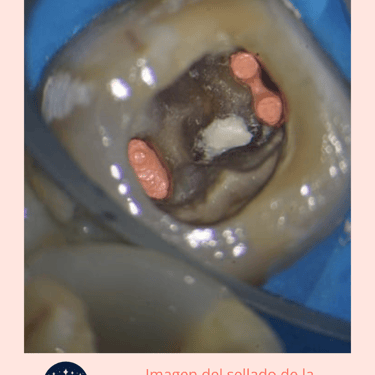

Acceso al Conducto: Se hace una apertura en la corona del diente para acceder al conducto radicular y a la perforación.

Sellado de la Perforación: La perforación se sella con materiales biocompatibles específicos para endodoncia, como MTA (Agregado de Trióxido Mineral).

Relleno y Sellado: El conducto radicular se rellena y se sella para completar el tratamiento endodóntico.